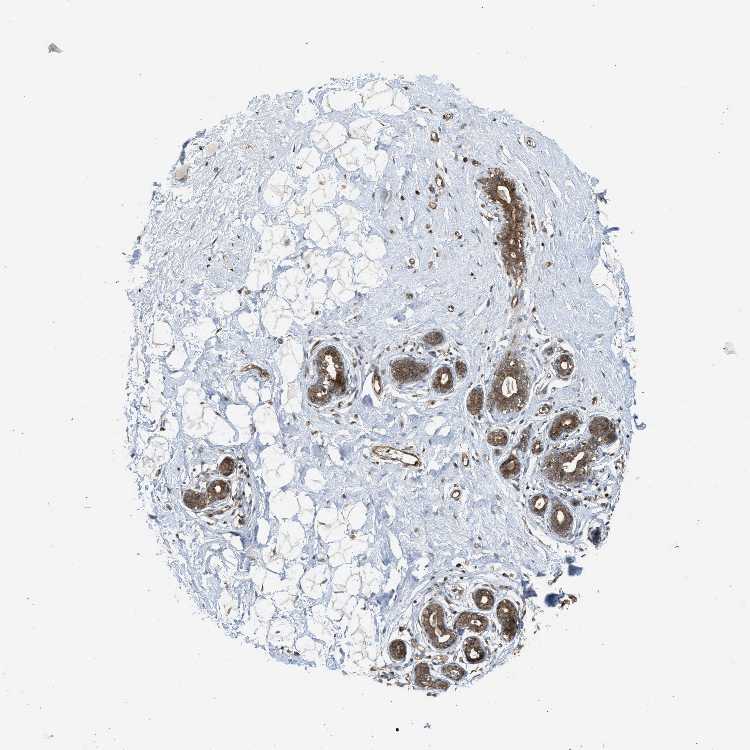

BREAST - Antibody stainingi

Antibody staining in the annotated cell types in the current human tissue is reported as not detected, low, medium, or high, based on conventional immunohistochemistry profiling in selected tissues. This score is based on the combination of the staining intensity and fraction of stained cells.

Each image is clickable and will lead to virtual microscopy that enables deeper exploration of all samples and also displays staining intensity scores, fraction scores and subcellular localization as well as patient and tissue information for each sample.

Antibody HPA009985Antibody CAB017804

Adipocytes Not detectedLow

Glandular cells HighHigh

Myoepithelial cells HighHigh